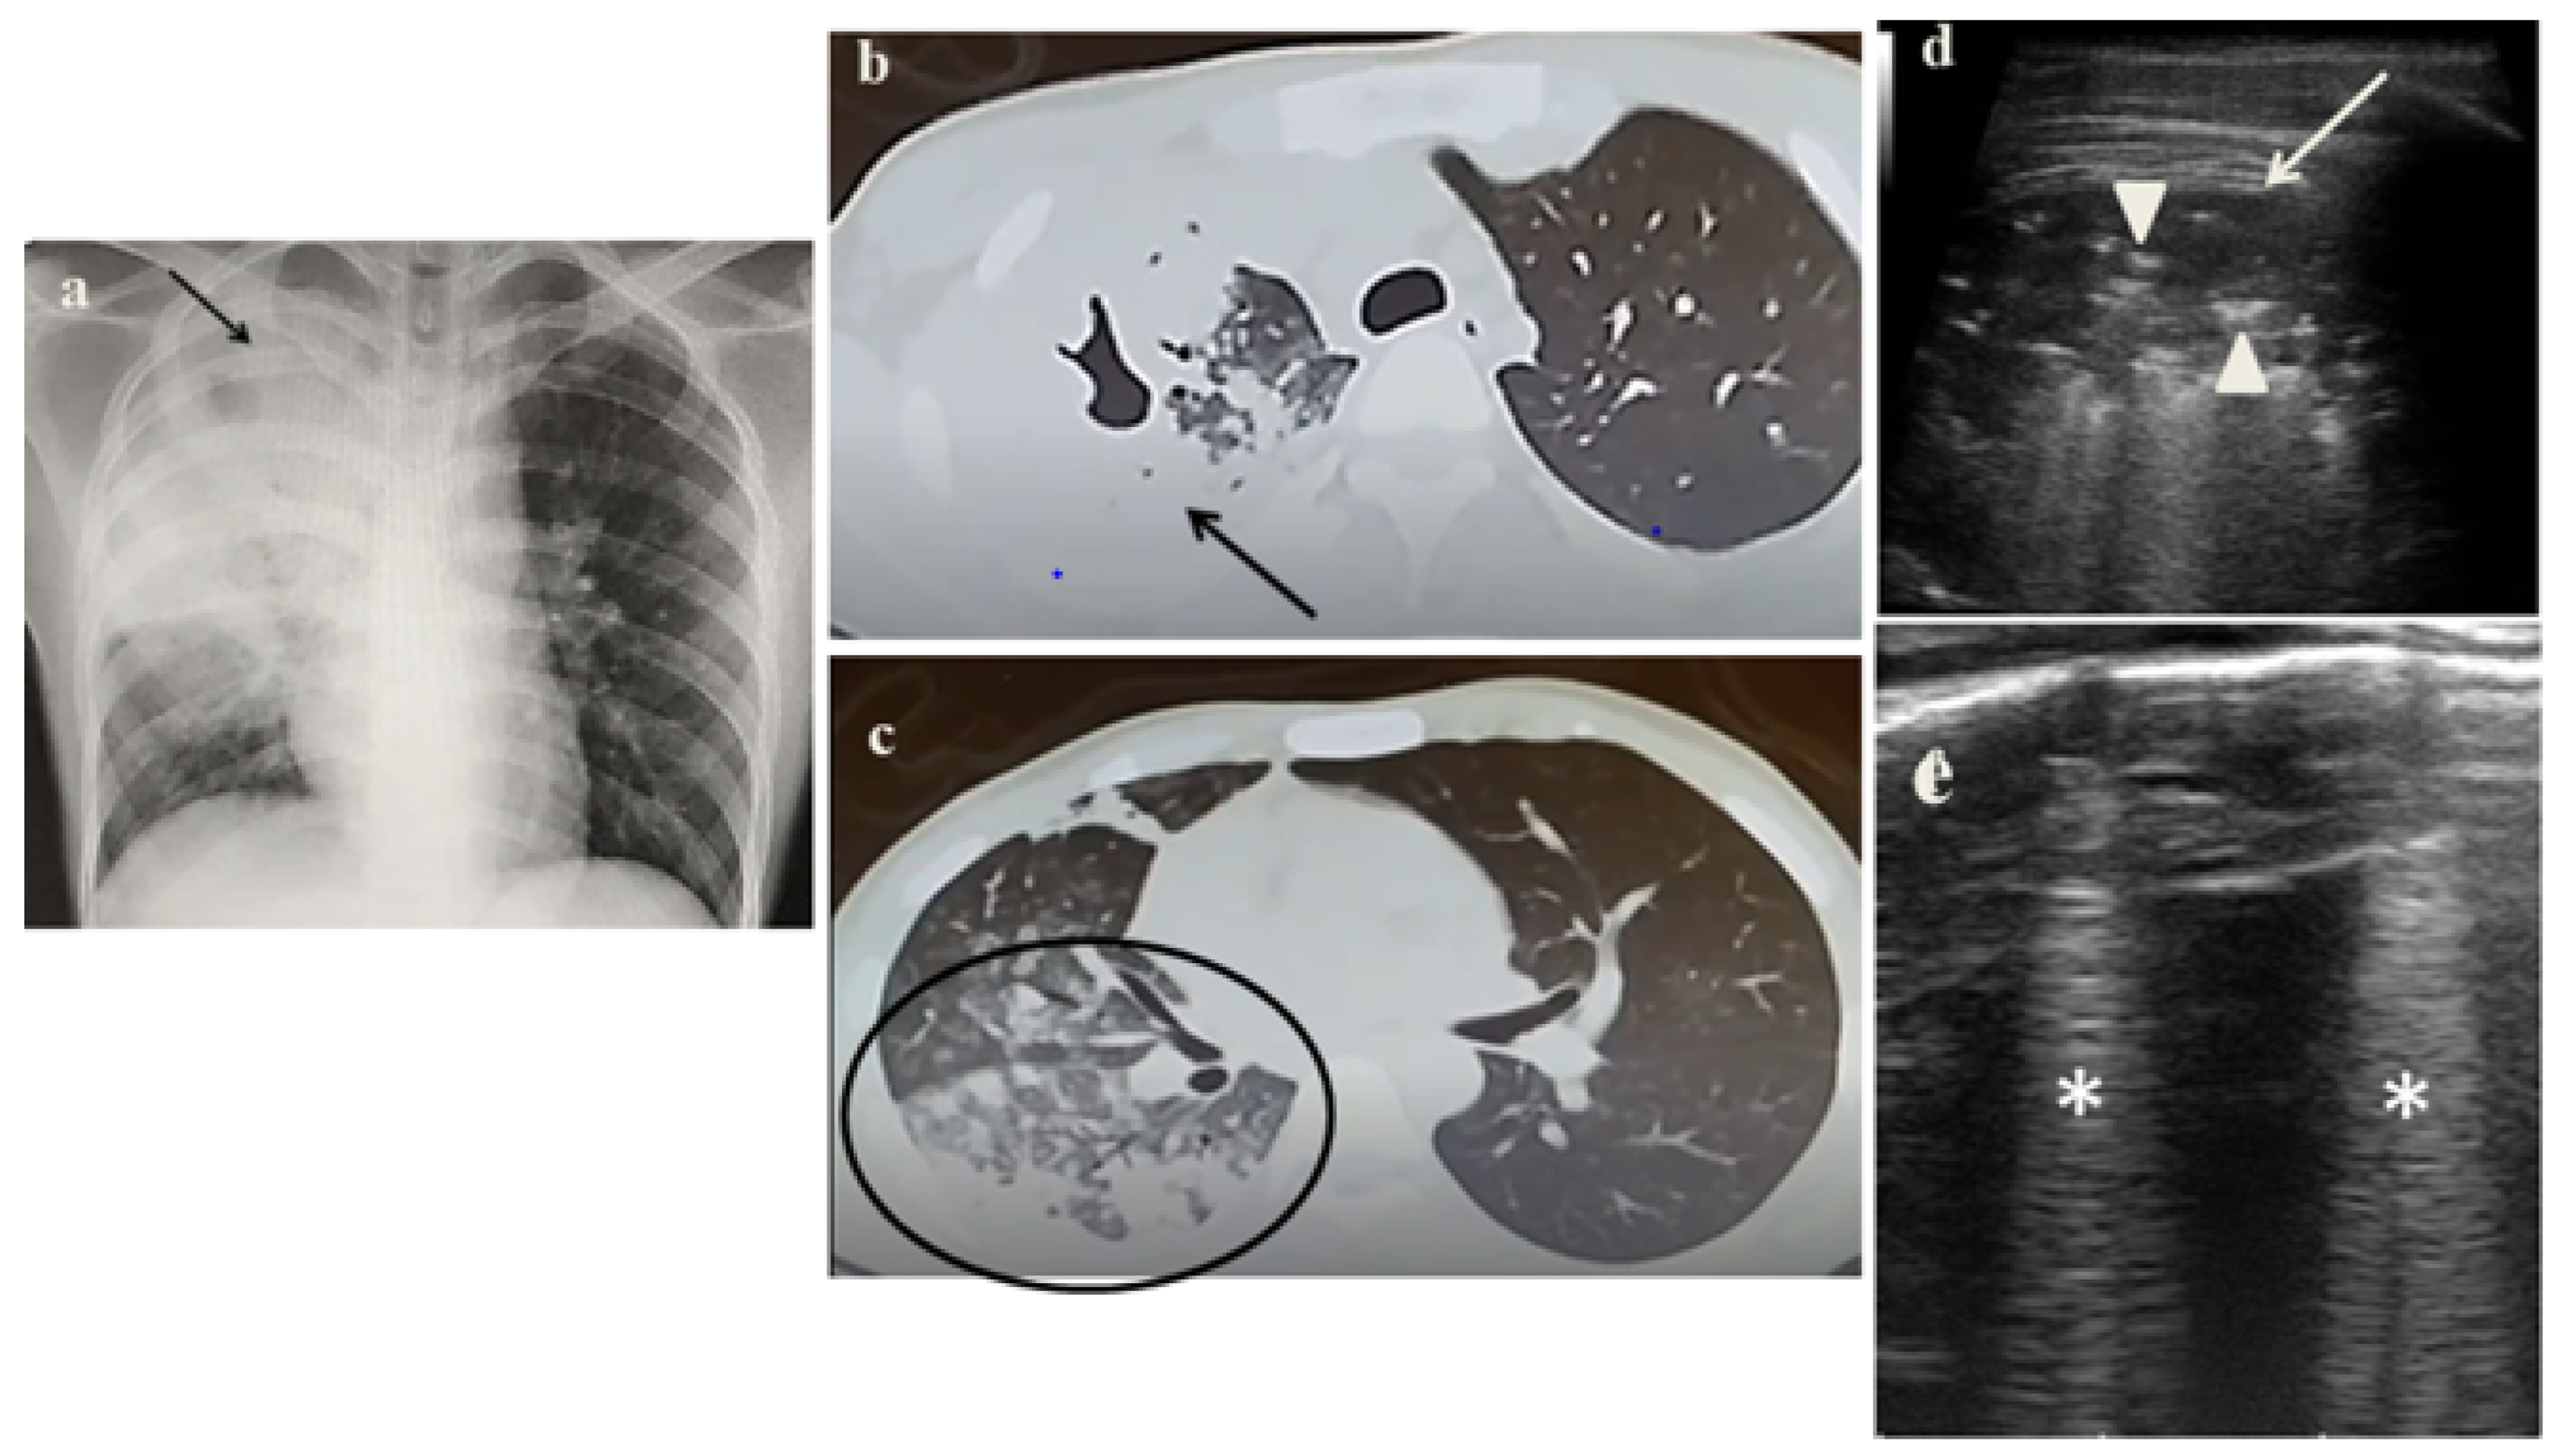

2.1. Case 1

- It identified in cases 1 and 3 large consolidations (Figure 1c and Figure 3c) with significant air content documented by thickened aerial broncograms. We have noticed that the latter have different characteristics compared to the air bronchograms present in bacterial or viral pneumonia [9]. These large consolidations could represent the tubercular cavitation seen at chest CT, but all these findings still need to be studied to better clarify their meaning;

- It was not possible to evaluate the hilar lymph nodal disease (Figure 1b), the hallmark of pediatric PTB, because of the interposition of air between the ultrasound and hilar lymph nodes; and